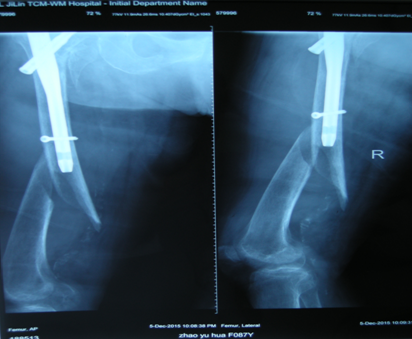

骨折术后再发骨折的手术治疗(骨科:刘菲)

患者老年女性,74岁,二次入院前5个月因外伤致右髋部疼痛,关节活动受限,拍片提示右股骨转子间粉碎性骨折,而入院行手术治疗,术后恢复良好。二次入院时因在家中洗澡时摔伤,拍片提示股骨干骨折,骨折部位位于内固定物远端。

明确诊断后,经过全科医生的术前讨论,详细制定了手术方案,再次给予手术治疗,将原有内固定物取出,换加长型PFNA,并用锁定钢板给予坚强固定,手术用时3小时,顺利完成。

术后常规治疗,由于坚强固定,术后早期功能练习,未出现明显并发症,恢复良好,患者及家属对于治疗效果很满意。